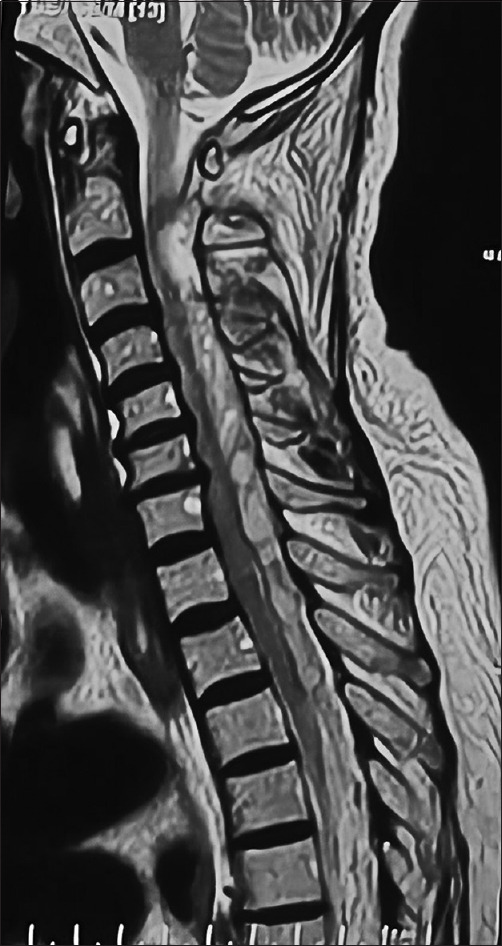

溶栓治疗后的灾难性自发性脊柱硬膜外血肿(SSEH)是神经外科和心脏病学的复杂交叉难题。本病例报告介绍了一名 66 岁女性在注射链激酶溶栓治疗下壁心肌梗死后迅速发生压迫性脊髓病的病例。SSEH 虽然罕见,但由于其可能导致永久性神经损伤和死亡,因此需要及时识别。讨论强调了 SSEH 的临床意义、解剖学考虑因素以及准确诊断和有效处理 SSEH 所需的多学科方法。结论强调了临床医生,尤其是实施溶栓疗法的心脏病专家,在溶栓后出现神经功能缺损的患者中考虑 SSEH 的必要性。

Catastrophic spontaneous spinal epidural hematoma (SSEH) following thrombolysis poses a complex intersection of neurosurgical and cardiological challenges. This case report presents the institutional experience of a 66-year-old female who developed rapid-onset compressive myelopathy after thrombolysis for inferior wall myocardial infarction with injection streptokinase. SSEH, although rare, demands prompt recognition due to its potential for permanent neurologic injury and mortality. The discussion highlights the clinical significance, anatomical considerations, and multidisciplinary approach requisite for accurate diagnosis and effective management of SSEH. The conclusion underscores the necessity for clinicians, particularly cardiologists administering thrombolytic therapies, to consider SSEH in postthrombolysis patients presenting with neurological deficits.